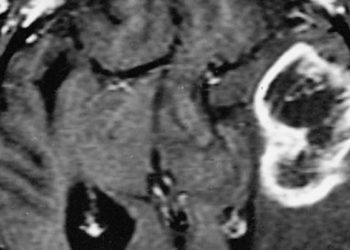

The Scan by 2 Minute Medicine®: Patient Zero: Immunotherapy for Brain Tumors?, Over-the-Counter Birth Control, Florida Supreme Court Deals a Devastating Blow to Abortion Access, Schwarzenegger’s Post-Pacemaker Update on Instagram